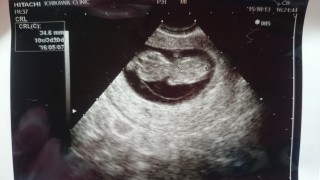

逆さまになってる赤ちゃんかわいい。 初めて心音も聞かせてもらえて感動(;∀;) 手足動いてるの見たいなって期待してたけど残念…笑 次はみれるといいなぁ~笑 大きさは36.1mmです。

つわりでご飯食べれないけど、赤ちゃんはぐんぐん大きくなってくれてます!10w1dで34.6mm!二週間後が楽しみ!